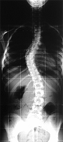

Anaëlle est une jeune fille qui est amenée par sa maman la 1ère fois en consultation d'orthopédie infantile à l'âge de 14 ans.

Elle est suivie depuis plus d'1 an et traitée par "ostéopathie" pour une scoliose de la jeune fille (dite scoliose idiopathique).

La radiographie de la colonne retrouvait:

une déformation thoraco-lombaire majeure avec un angle de Cobb de 40° (angle de déformation entre les vertèbres qui penchent le plus) !!!!!!!!

En reprenant les anciens documents radiographiques, ont pouvait observer l'aggravation progressive de cette scoliose au fil du temps, c'est-à-dire pendant la phase d'accélération de la vitesse de croissance de l'adolescence.

En conclusion:

non seulement l'"ostéopathie" n'avait eu aucune action pour empêcher l'aggravation de la scoliose (c'est qui n'est pas une surprise), mais l'ostéopathe a regardé passivement cette scoliose augmenter au fil du temps sans aucune réaction, ni bon sens de base consistant à l'envoyer consulter un spécialiste.

Ce jusqu'au boutisme dans l'incompétence est quasi-criminel puisque cette scoliose va nécessiter un traitement par corset plâtré réducteur, puis corset classique, en attendant probablement une intervention chirurgicale.

En effet, le moment de surveillance passive ostéopathique (avec pour la famille illusion de traitement) correspond exactement au moment idéal où cette scoliose aurait pu bénéficié d'un véritable traitement orthopédique médical par corset, évitant ainsi son aggravation et son évolution lente vers une chirurgie.

En matière de scoliose, il n'est pas possible de revenir en arrière, et une fois que l'on est passé à côté du bon moment pour traiter, c'est trop tard.

Le Dr Roger Parot, chirurgien orthopédiste pédiatre, rappelle que la chirurgie du rachis est une chirurgie à risque vital (risque de mourir), mais aussi une chirurgie à risque fonctionnel neurologique (risque d'être paralysé).